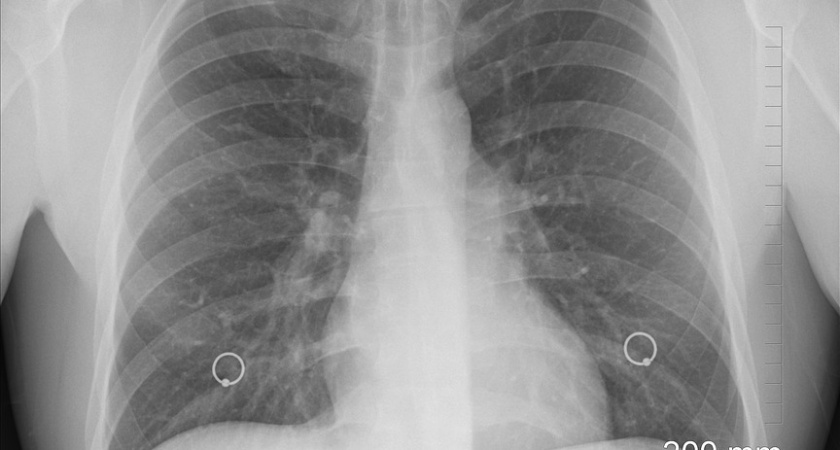

Оборудование необходимо при лечении осложнений коронавируса

Воронежской области выделят 34,2 млн рублей федеральных средств на аппараты для искусственной вентиляции легких (ИВЛ), сообщили в облдуме по итогам заседания 26 марта. Это оборудование используется при лечении тяжелых стадий коронавирусной инфекции.

Деньги выделят из резервного фонда правительства РФ. Оборудование доставят в медучреждения региона. На данный момент в области насчитывается 348 аппаратов ИВЛ.